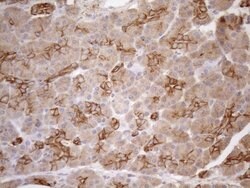

KRT16 Monoclonal Antibody (OTI1G1), TrueMAB™, OriGene

KRT16 is a member of the keratin gene family. The keratins are intermediate filament proteins responsible for the structural integrity of epithelial cells and are subdivided into cytokeratins and hair keratins. Most of the type I cytokeratins consist of acidic proteins which are arranged in pairs of heterotypic keratin chains and are clustered in a region of chromosome 17q12-q21. This keratin has been coexpressed with keratin 14 in a number of epithelial tissues, including esophagus, tongue, and hair follicles. Mutations in this gene are associated with type 1 pachyonychia congenita, non-epidermolytic palmoplantar keratoderma and unilateral palmoplantar verrucous nevus.Specifications

| Immunohistochemistry (Paraffin), Western Blot | |